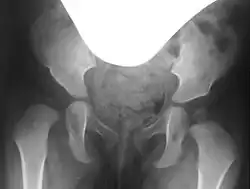

Hip dysplasia on the right (left in the image), with a steep acetabulum and absent acetabular rim, and a poorly formed femoral head

In hip dysplasia, the femoral head lacks sufficient lateral and anterior coverage, known as the acetabular rim. This inadequate coverage can cause the femoral head to slip upward and, depending on the severity, may lead to dislocation of the hip.[3]